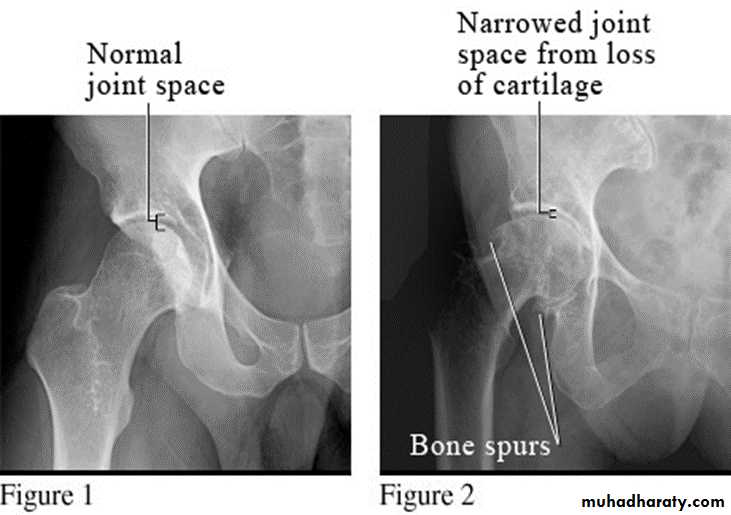

Degenerative Arthritis

Degenerative joint disease (DJD) = osteoarthritis (OA).

Radiographic features:

Five hallmarks:

* Narrowing of joint space, usually asymmetrical

*Subchondral sclerosis

* Osteophytes